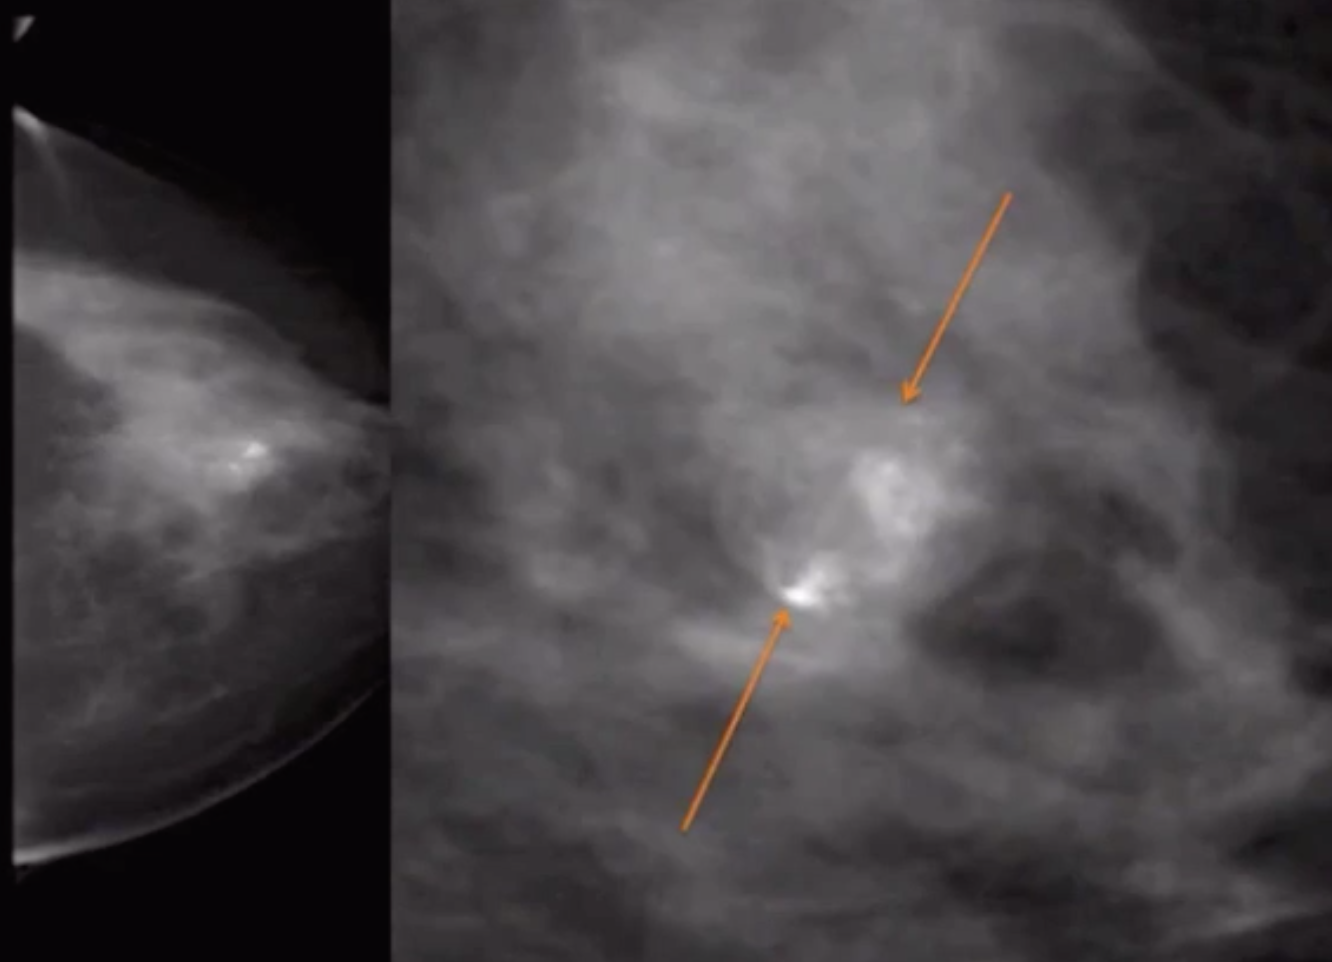

Fibroadenoma

• Round well circumscribed mass with central scar

• Largely hypoechoic with hyper-echoic central scar

• Mass in pre-menopausal woman (estrogen dependent)

• If seen in an older person it will have bulky popcorn calcs, with increased calcs in it over time